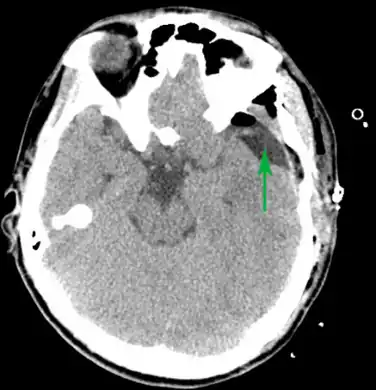

Male with complicated arachnoid cyst

Arachnoid cyst as seen on a CT image of the brain

Diagnosis is principally by MRI. Frequently, arachnoid cysts are incidental findings on MRI scans performed for other clinical reasons. In practice, diagnosis of symptomatic arachnoid cysts requires symptoms to be present, and many with the disorder never develop symptoms.